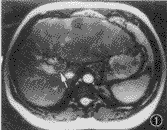

图1~4 男,41岁,肝左叶巨块型肝细胞癌,门静脉瘤栓(箭头)。图1和图2为true-FISP横断及冠状面T2.WI,门静脉呈亮信号,腔内瘤栓清晰显示;图3为TSE T2WI,门静脉瘤栓呈略高信号肿块,显示不及true-FISP;图4为对比增强门静脉MR血管造影,证实门脉瘤栓存在

1.图像质量:图像质量分级评价结果见表1,与TSE序列T2WI相比,true-FISP序列T2.WI可清楚显示肝静脉、门静脉主干及主要分支或属支,血管在此序列上呈高信号,病变对门静脉及肝静脉的侵犯能清晰显示(图1~4)。尽管应用了脂肪抑制,大多数病人的TSE图像仍有由于轻微呼吸运动造成的伪影,而true-FISP图像即使病人不能很好屏气,也没有明显的呼吸运动伪影。靠近肠道(如胆囊窝及其周围)及膈肌面(特别是膈面不平滑的病人)的部分肝脏区域,在true-FISP图像上受气体干扰可出现圆形伪影,酷似肝内病灶或胆囊结石,也可掩盖肝内病灶,TSE图像上不出现类似的伪影。对于脏器的轮廓及肝外结构如胆管、肠管、血管、组织间隙等的显示,true-FISP序列也明显优于TSE序列。

true-FISP选用很短的TR和TE,流动效应几乎可以忽略不计,血液的长T2特点可以得到很好的体现[7,8]。在true-FISP T2.WI中,动脉、静脉都呈现高信号,门静脉系统及肝静脉的解剖结构和病变的侵犯都能清楚地显示,明显优于TSE序列(图1~3),这对于病变范围确定、病变分期分级及制定肝脏肿瘤的治疗方案都有着重要的指导意义,门脉系统的充分显示还有利于门脉高压及其侧支循环的评价,这是目前其他常规MRI序列无可比拟的。